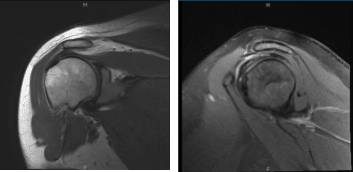

The patient presented MRI results of left shoulders that showed Moderate grade partial-thickness bursal surface tear of the distal supraspinatus tendon with accompanying subacromial subdeltoid bursitis.

MRI-3T Left Shoulder non-contrast